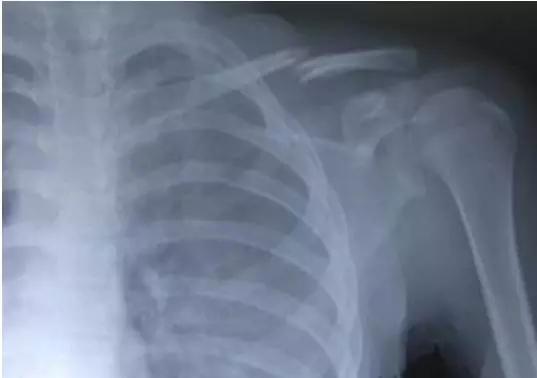

图2:锁骨骨折愈合过程中的骨痂形成